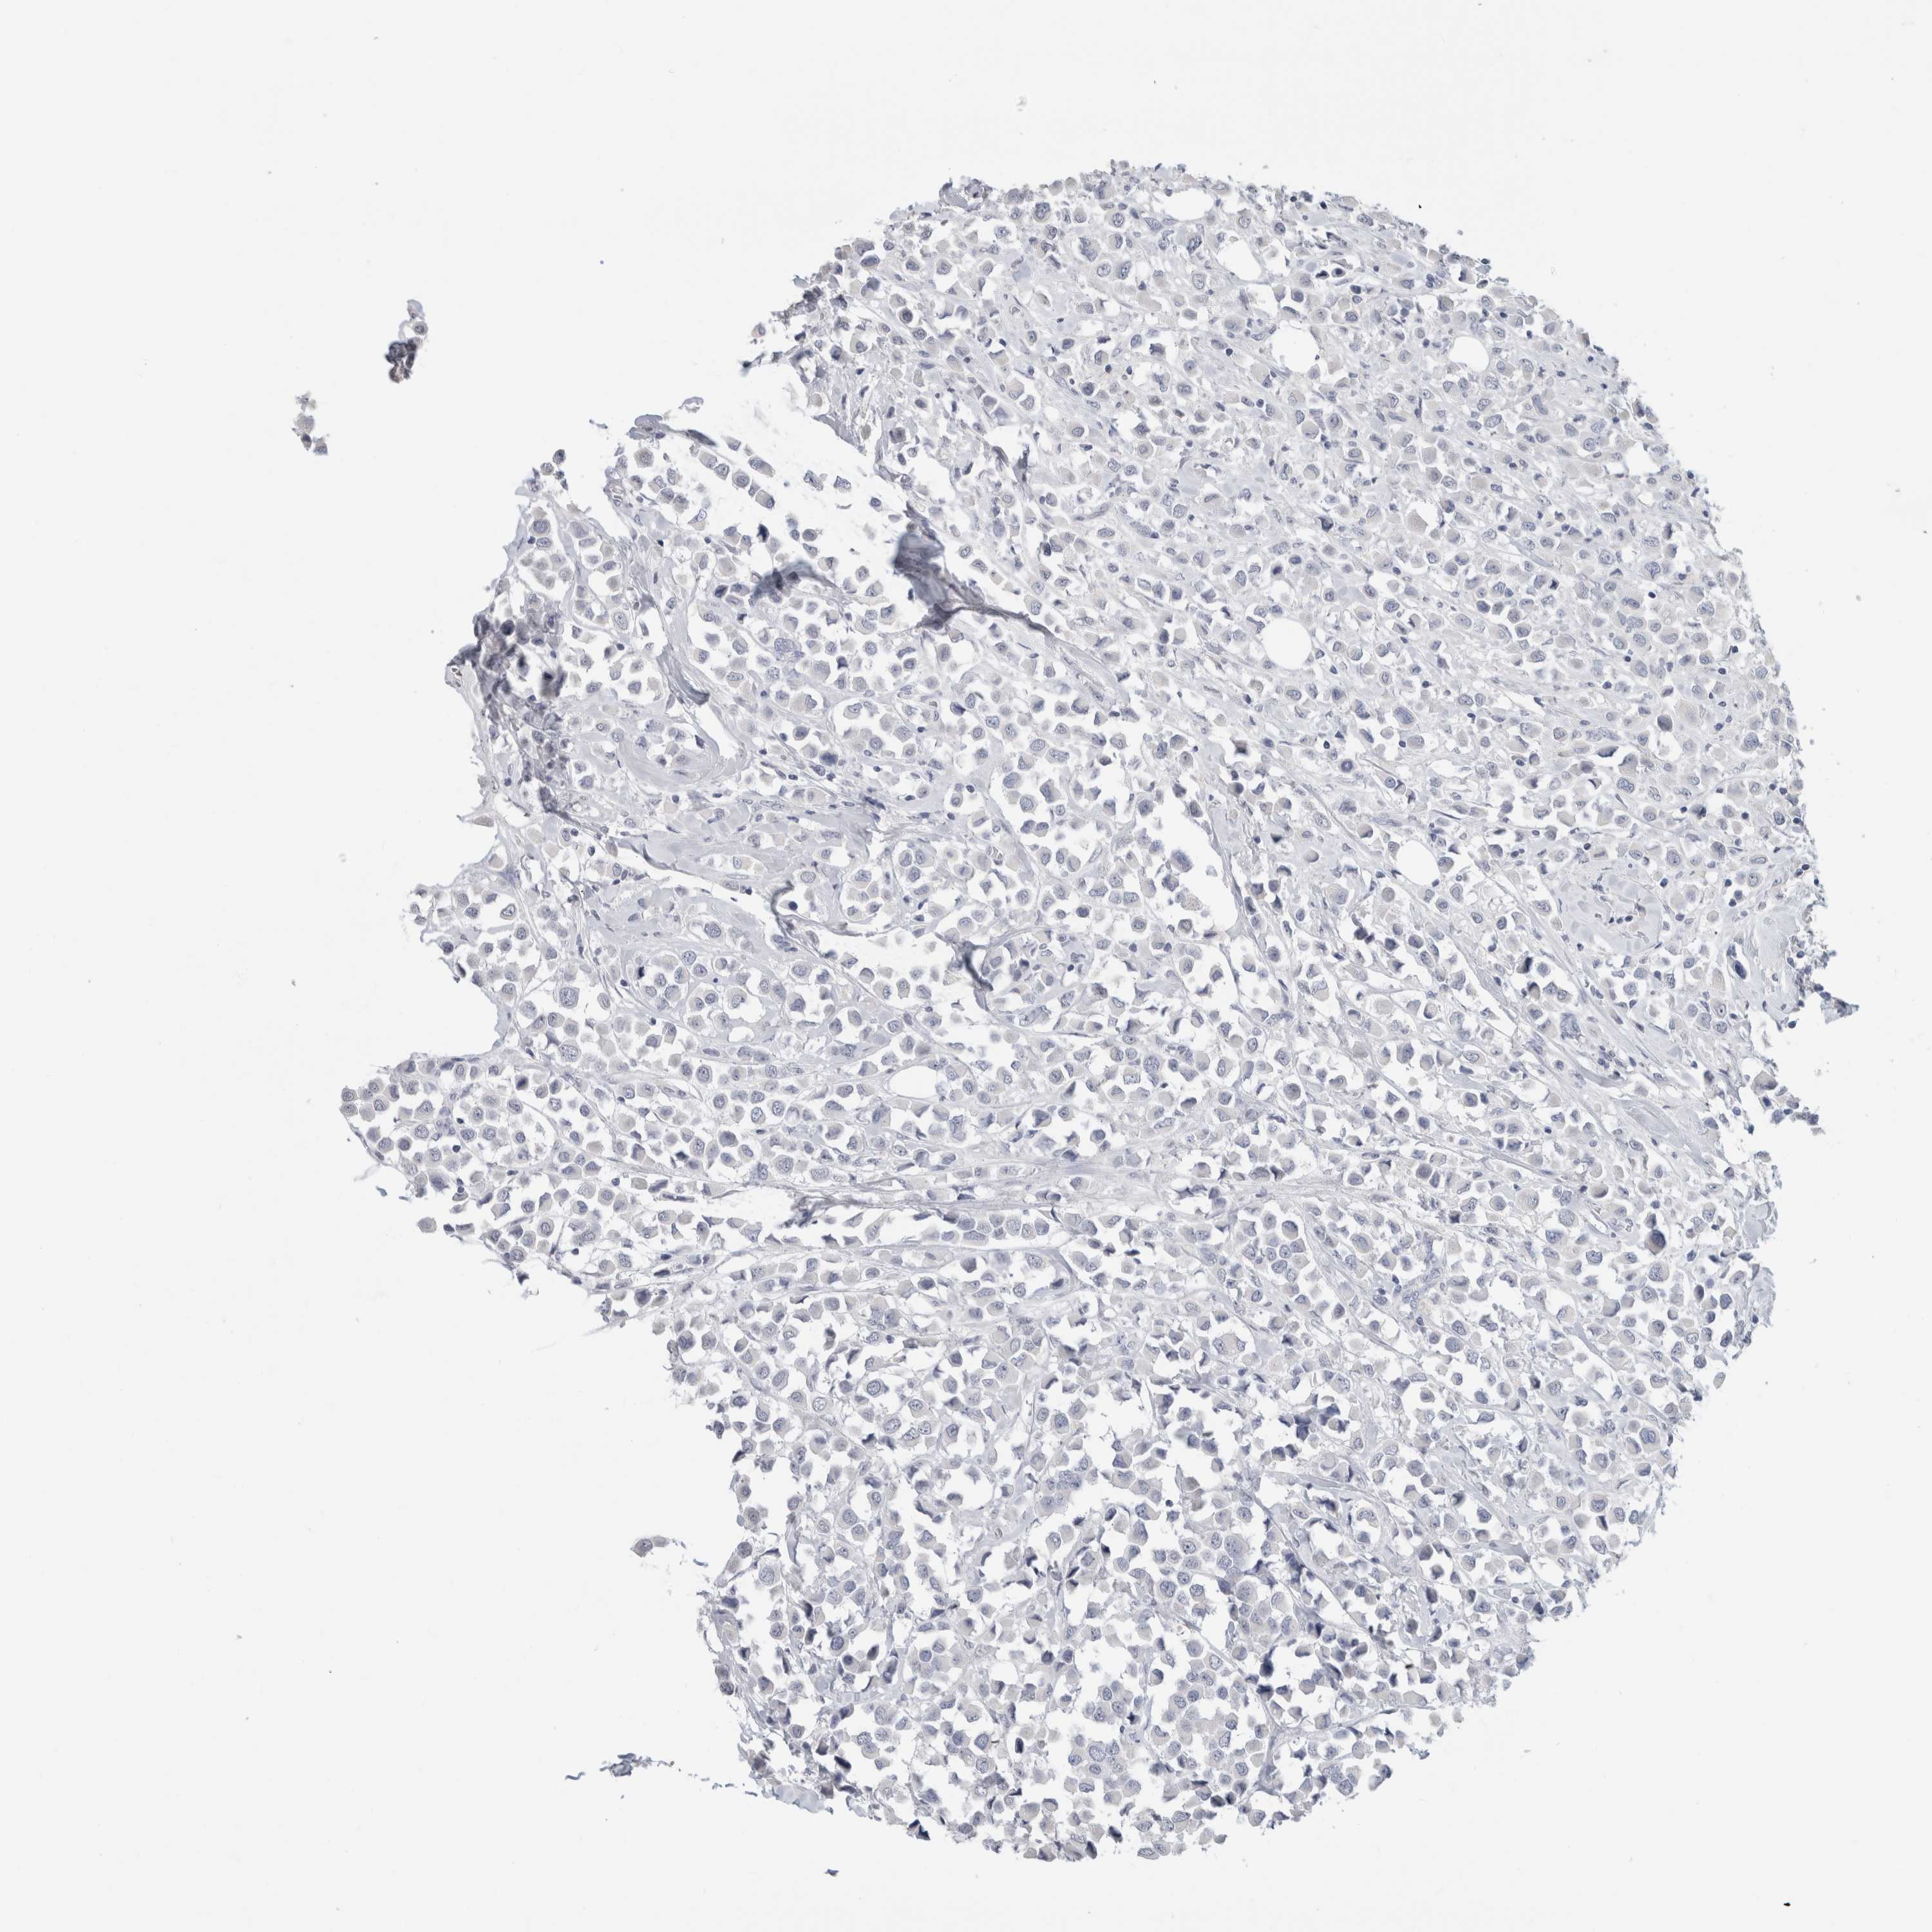

CANCER BREAST CANCER Show tissue menu

BRCA TCGA BRCA VALIDATION PROTEIN EXPRESSION